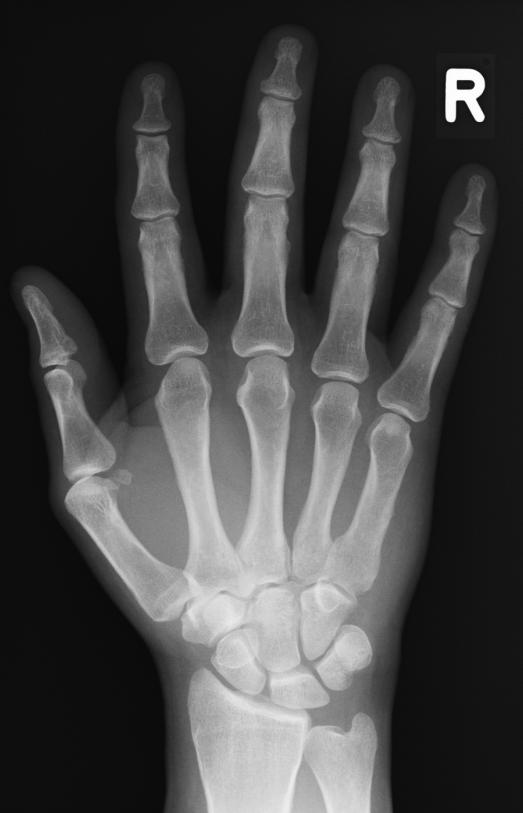

Digitiales Röntgen

Die digitalisierte Radiographie unterscheidet sich im Prinzip nicht von der gewohnten Röntgenaufnahme: Die Röntgenstrahlen belichten hinter dem Patienten einen Film, es entsteht ein Röntgenbild.

An die Stelle des herkömmlichen Films tritt jetzt eine Speicherplatte. Ein Computer wertet die Speicherplatte aus. Ein elektronisches Archiv sammelt die Aufnahmen. Sie sind damit jederzeit erneut für Sie verfügbar. Wiederholungsaufnahmen wegen nicht auffindbarer Bilder gehören der Vergangenheit an. Das ist für Sie eingesparte Röntgendosis.

Das Bild kann noch nachbearbeitet werden. Fehlbelichtungen werden ausgeglichen, Wiederholungsaufnahmen wegen schlechter Belichtung gibt es nicht. Das ist wieder eingesparte Dosis.